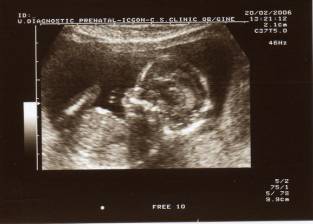

Et

me voilà maintenant de profil… Je mesure seulement 6 cm.